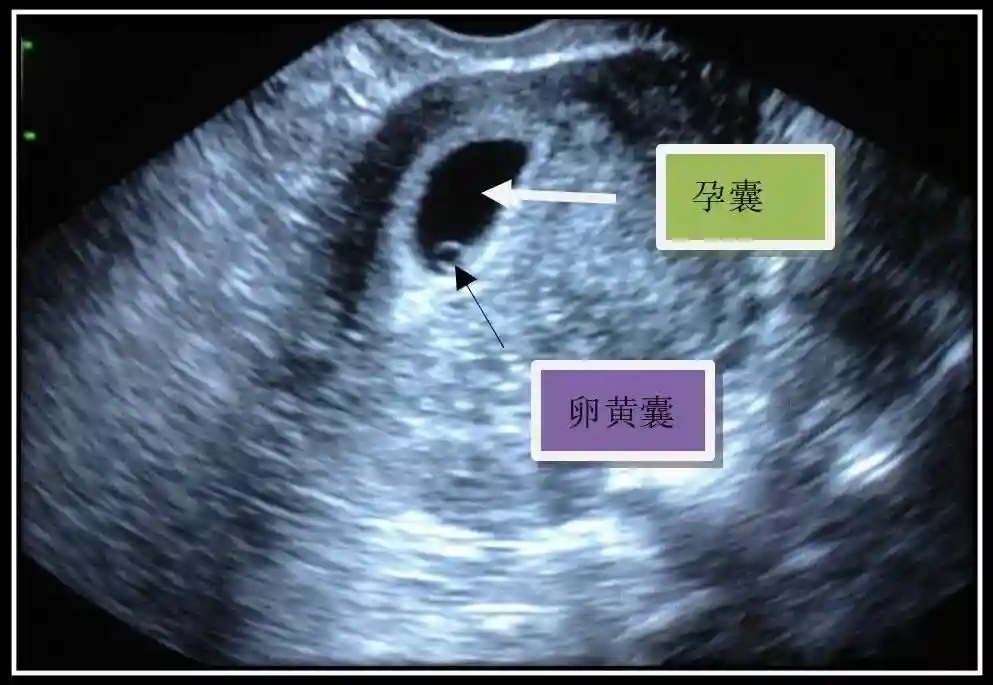

2??卵黄囊:是妊娠囊内第一个解剖结构,直径<7mm。表现为小环状,中央为无回声,囊壁薄,内透声好。卵黄囊位于胚胎旁胚外体腔内。卵黄囊通常在孕5-6周时出现,5-10周稳步增长,一般不超过7mm,至12周消失。妊娠囊的大小与卵黄囊之间有一定关系,妊娠囊平均直径> 8 mm 时,经阴道超声均应显示卵黄囊,妊娠囊平均直径> 18 mm 时,经腹超声均应显示卵黄囊。